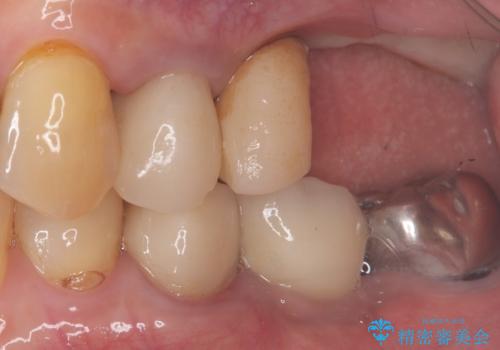

- 主訴:食べ物噛むと左奥歯が痛い

左上6番目の歯が根っこ部分で破折しており、噛むたびに痛みが生じる状態でした。

保存不可能と判断し、抜歯から骨ができるのを3か月待ってインプラント治療を行いました。

歯根破折により抜歯となり、インプラント治療(一回法)にて補綴修復を行いました。

抜歯から3か月程骨ができてくるのを待ってからインプラントを埋入しています。

埋入時には上顎洞粘膜を数ミリ挙上しています。